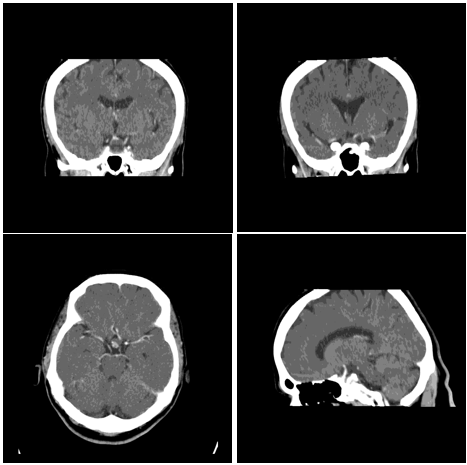

A CT scan can show calcification better than other imaging, while MRI can appreciably delineate the extent of the tumor and its relation to the hypothalamus and adjacent structures, therefore, it is sound imaging preoperatively; moreover, MRA can differentiate the tumor mass from vascular malformations like aneurysm (Figure 2).15,16

MRI of the pituitary 05.02 (Figure 4).

The imaging findings are those of Craniopharyngioma (Figure 4).